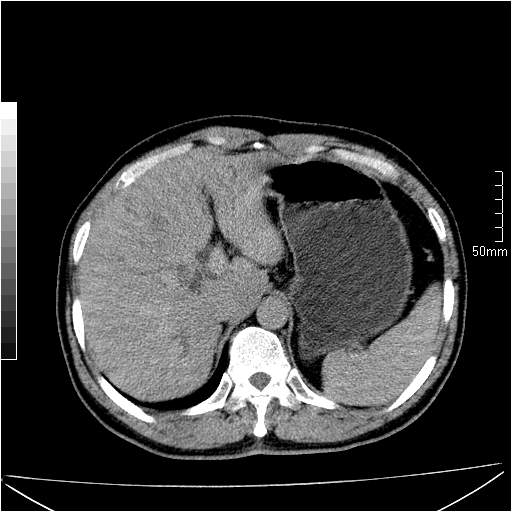

男性,54岁,皮肤黄染,搔痒一周余.b超示肝左叶回声异常.初步诊断1胆总管下段结石2胆囊结石伴慢性胆囊炎请各位战友帮忙看一下肝脏多发低密度如何解释恰当.增强效果不是很好.请大家见谅.

胆总管及肝内胆管扩张,考虑是结石!但,肝内的低密度区增强不明,可能是肝ca,因为肝ca在增强时呈快进快出.另年胆总管扩张原因,可以考虑一下是不是,胆管ca.再次要考虑肝内的低密度是否为海绵状血管瘤所致!

首先,胆总管下端结石梗阻伴肝内胆管扩张可确定。

其次,增强动脉期肝静脉显影,肝实质密度不均。——此为右心功能不全引起肝淤血的表现。

另外,肝八段低密度占位,呈多灶性,考虑肝脓肿或肝癌可能,(图像质量欠佳)建议进一步检查。

由于胆囊窝内结构显示不清,肝脏病灶又邻近胆囊窝首先考虑胆囊癌肝受侵犯。而后因肝脏病灶强化有渐进改变,且相邻胆管扩张,故考虑肝胆管细胞癌待排。

左肝胆管细胞癌。

胆总管下端结石。